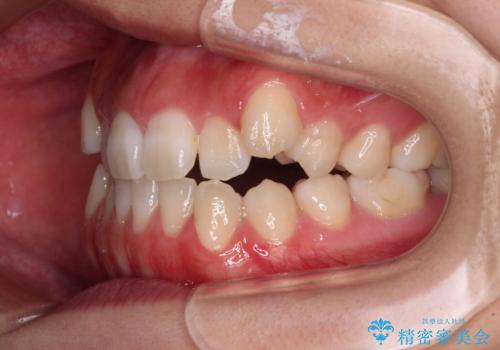

- 前歯の開咬と、上顎前歯の八重歯やデコボコを気にして来院された患者様です。

上顎歯列が狭窄していたため、急速拡大装置により上顎骨を側方に拡大し、その後ワイヤー装置にて矯正治療を行うこととしました。